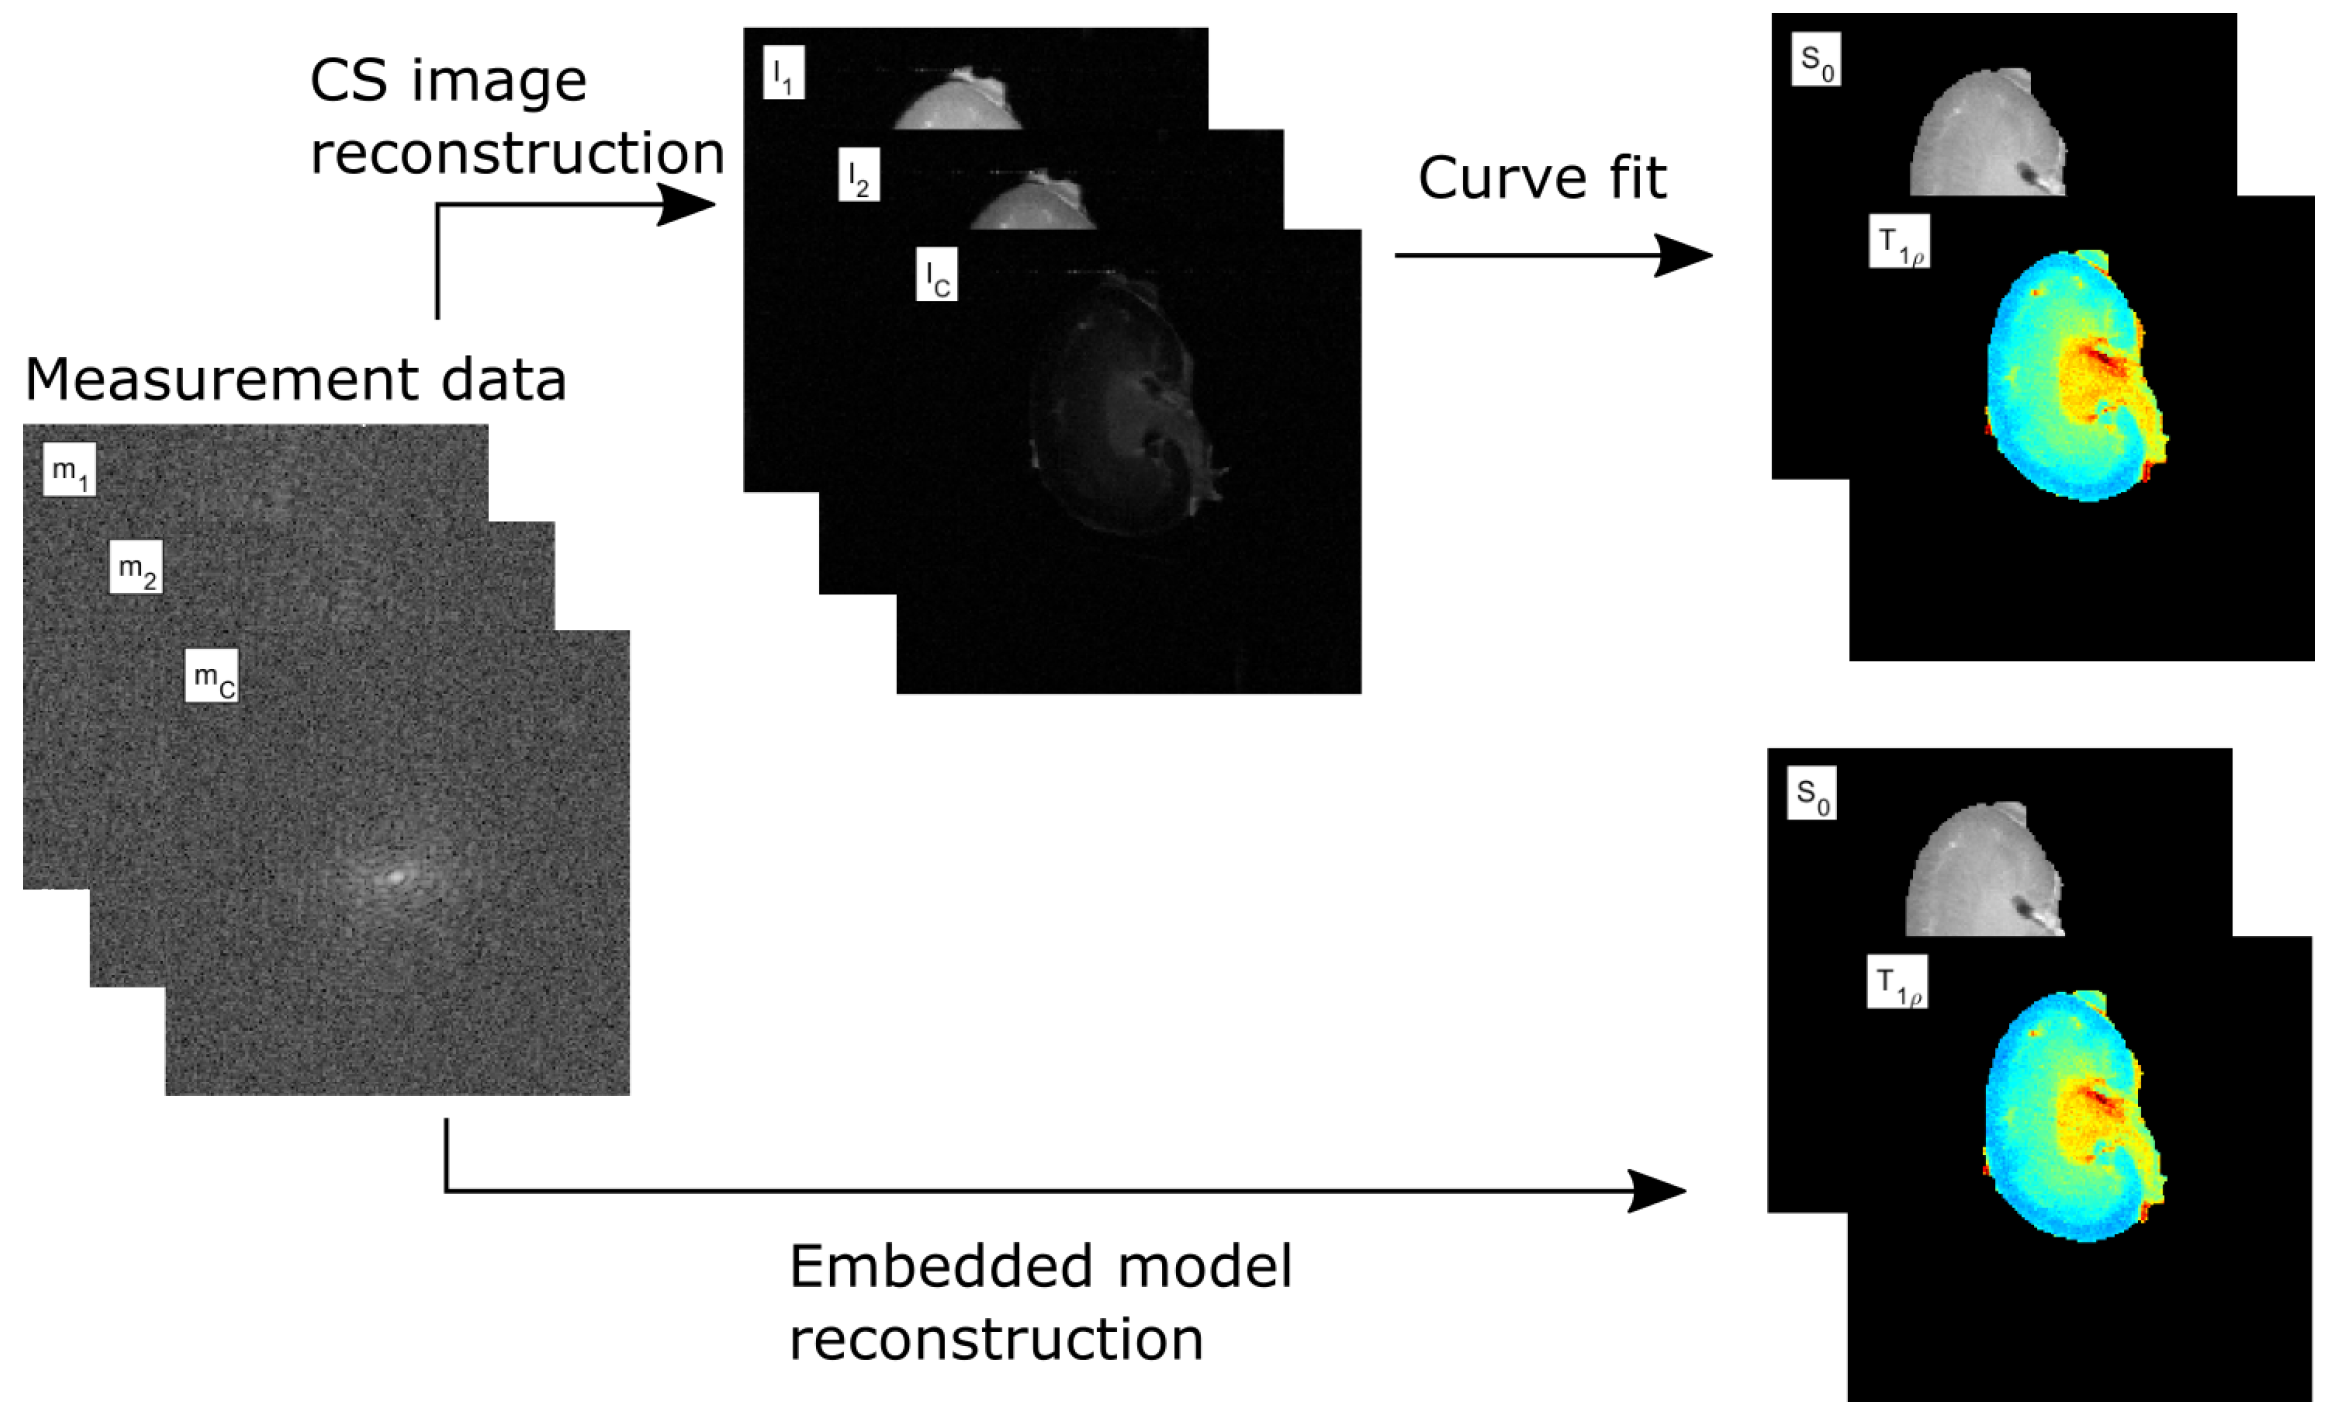

3.1. Simulated Golden Angle Radial Data

4.1. Simulated Golden Angle Radial Data